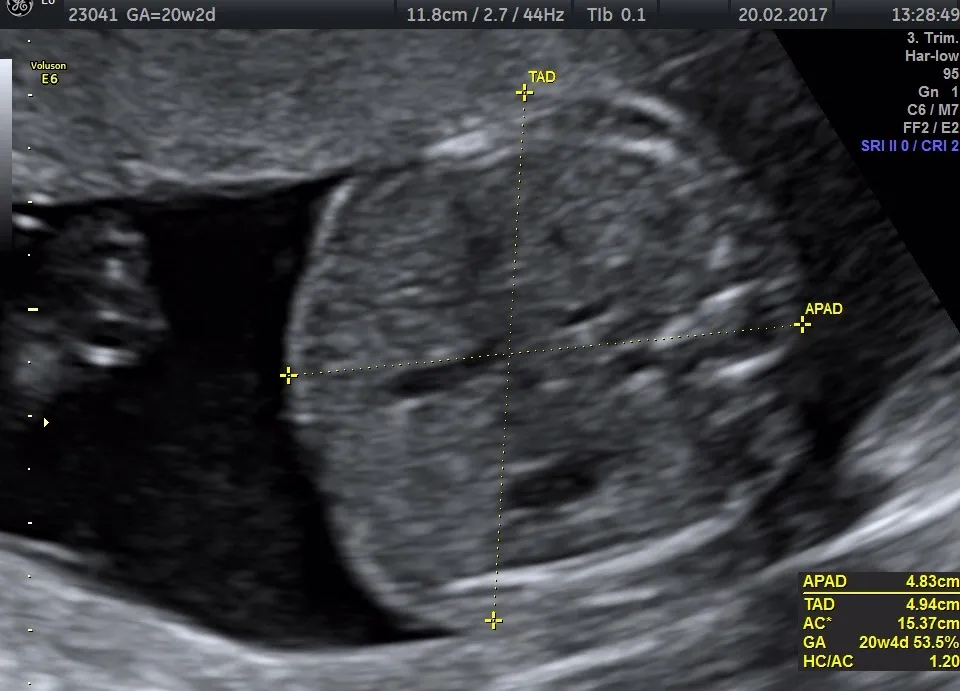

USG połówkowe (genetyczne): Co lekarz sprawdzi między 18. a 22. tygodniem?

USG połówkowe, często nazywane również genetycznym USG II trymestru, to jedno z najważniejszych badań w całej ciąży. Wykonuje się je między 18. a 22. tygodniem ciąży. Jego głównym celem jest szczegółowa ocena anatomii wszystkich narządów płodu, aby wykluczyć wady wrodzone. Lekarz dokładnie sprawdza serce, mózg, kręgosłup, nerki, kończyny i inne struktury. To także doskonała okazja, aby poznać płeć dziecka, jeśli sobie tego życzysz! Warto wiedzieć, że od czerwca 2024 roku w Polsce rozszerzono refundację badań prenatalnych przez NFZ dla wszystkich ciężarnych, niezależnie od wieku, co jest świetną wiadomością.